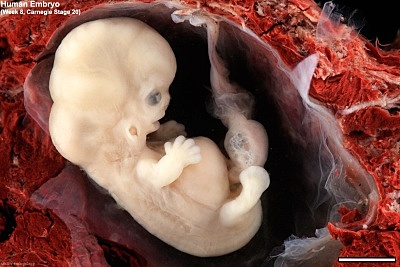

• Day 50- Secretory Phase (Stage 20)

Day 50- Secretory Phase (Stage 20)

During the 20th stage, the zygote has more of a baby appearance. One new feature during this stage is hearing.